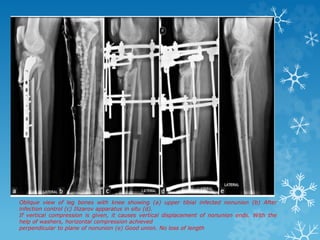

Oblique view of leg bones with knee showing (a) upper tibial infected nonunion (b) After

infection control (c) Ilizarov apparatus in situ (d).

If vertical compression is given, it causes vertical displacement of nonunion ends. With the

help of washers, horizontal compression achieved

perpendicular to plane of nonunion (e) Good union. No loss of length

Oblique view ofleg bones with knee showing (a) upper tibial infected nonunion (b) After infection control (c) Ilizarov apparatus in situ (d). If vertical compression is given, it causes vertical displacement of nonunion ends. With the help of washers, horizontal compression achieved perpendicular to plane of nonunion (e) Good union. No loss of length